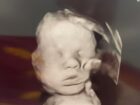

【衝撃】エコー写真に「神の手」出現!? 祈りが起こした奇跡か、それとも…

米ケンタッキー州のある女性が、妊娠中の超音波検...